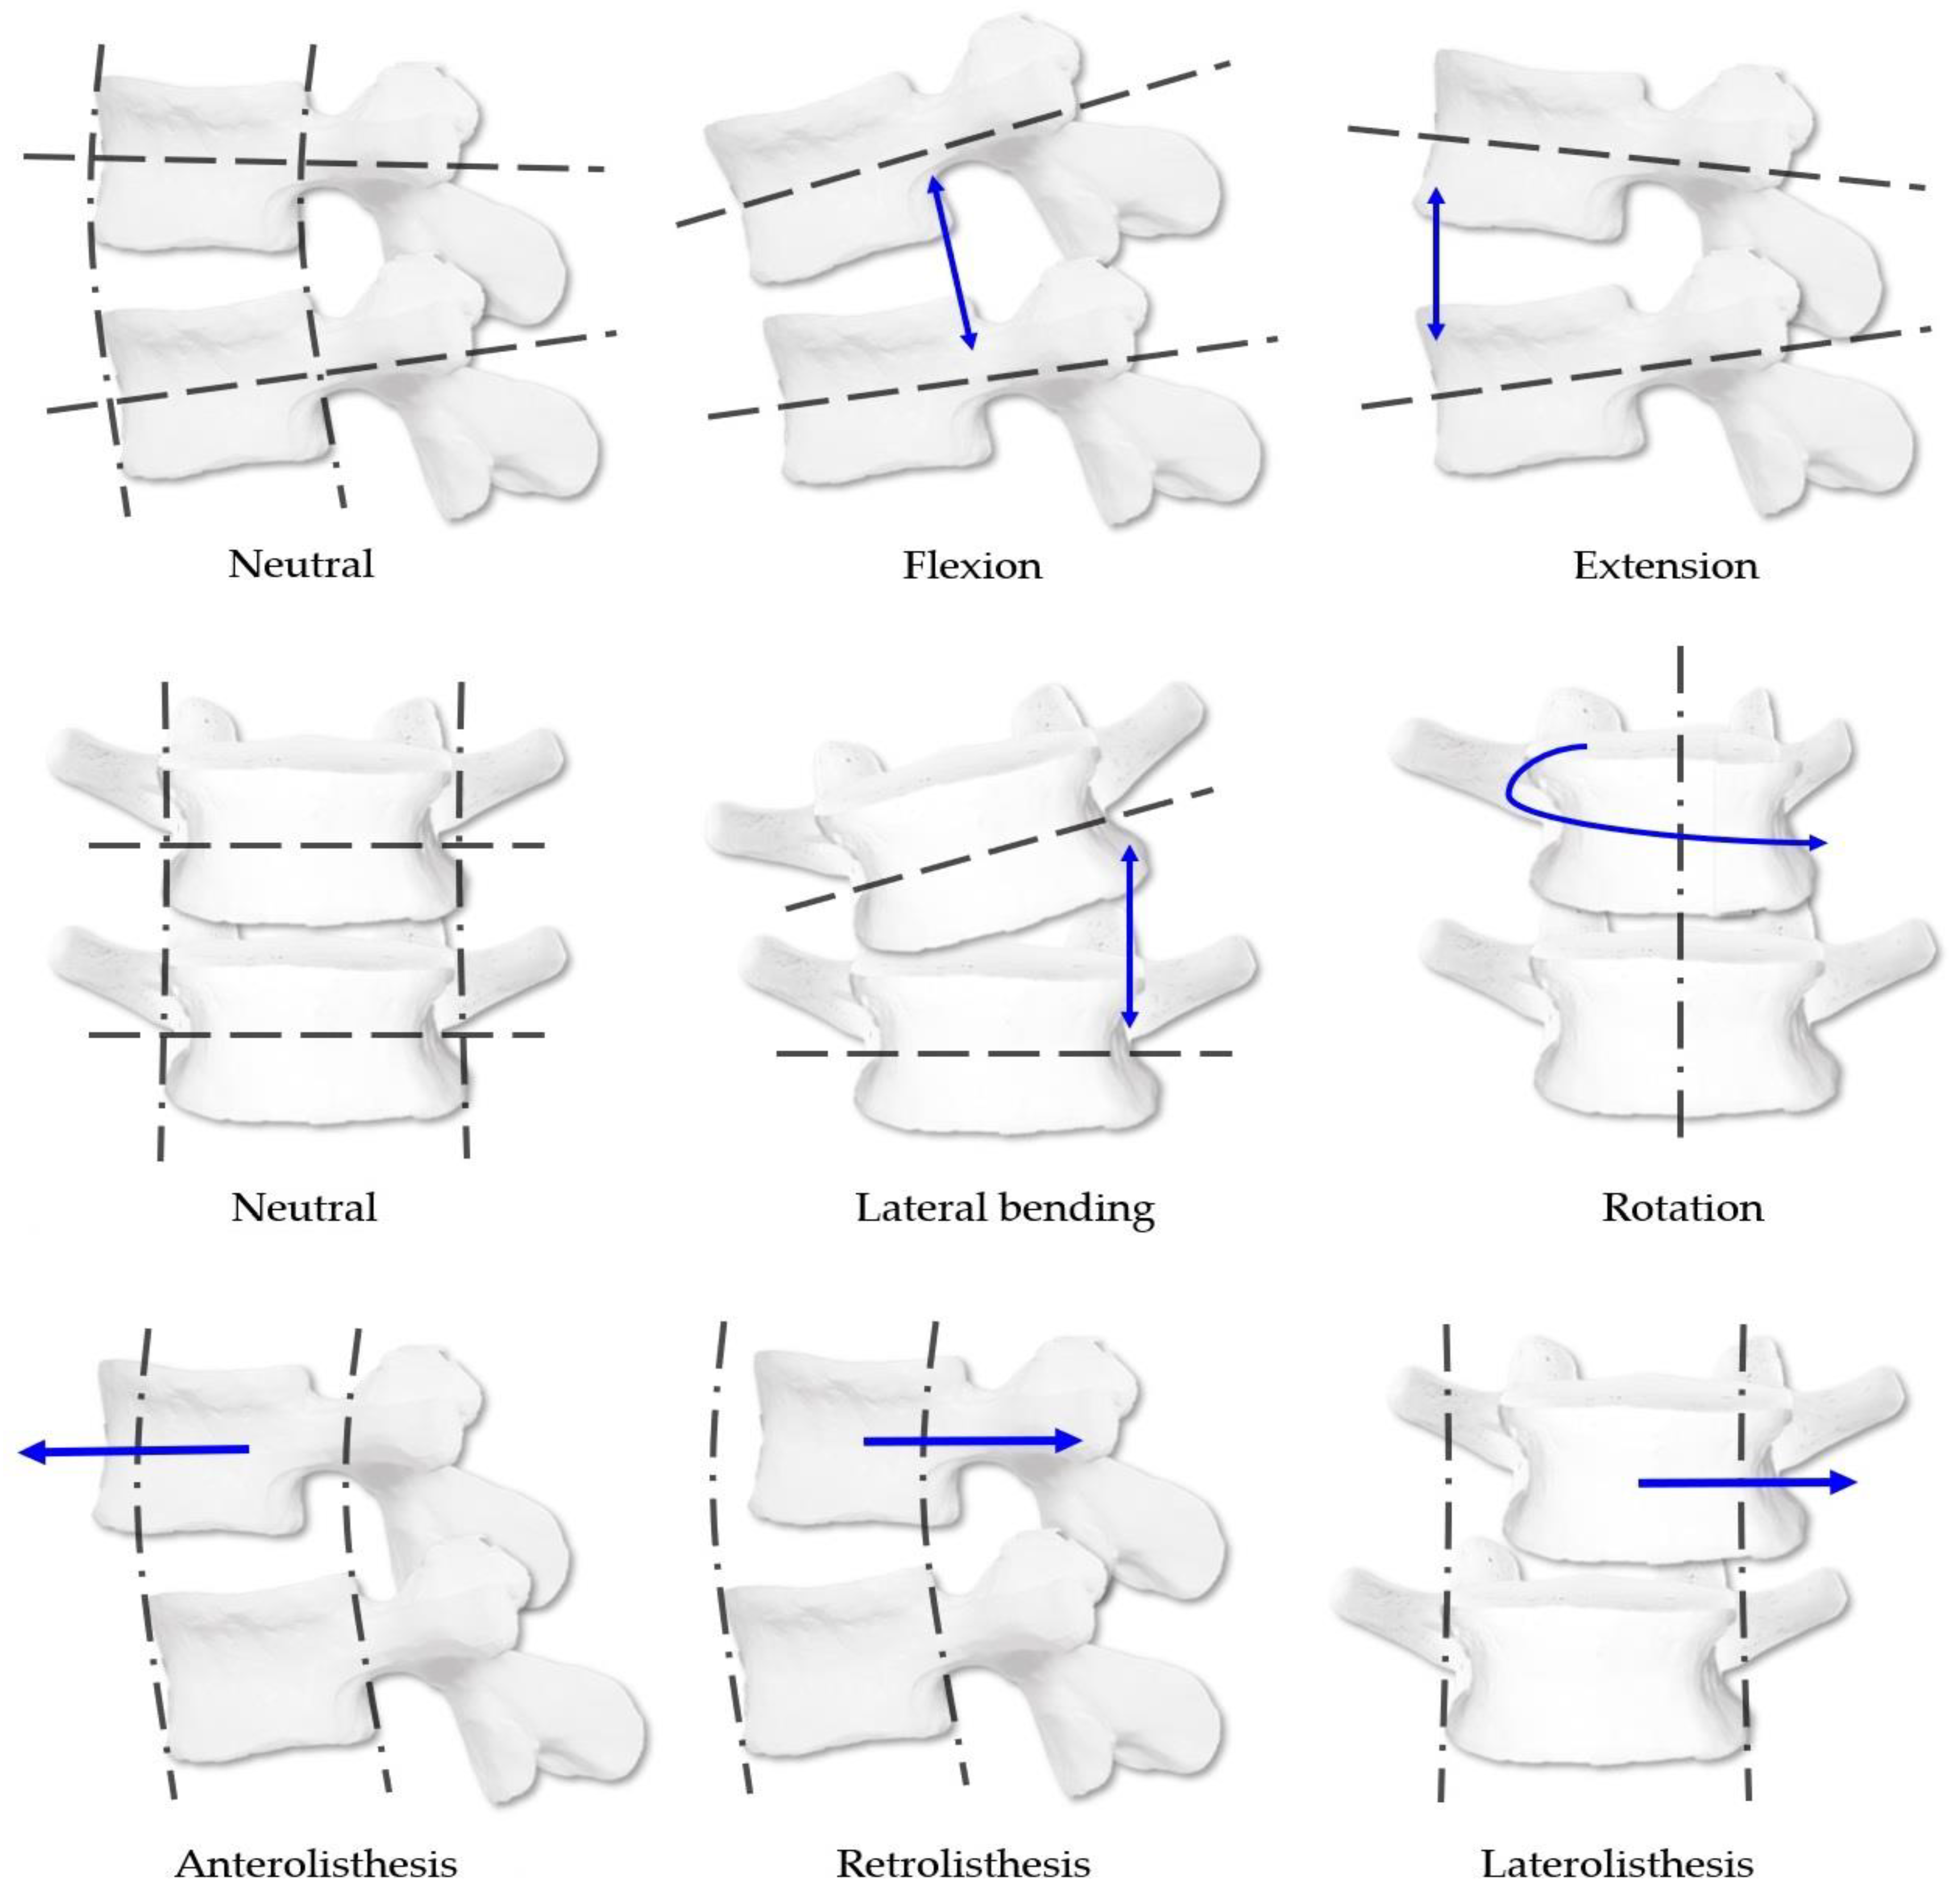

2.6.1. CMT Spinal Diagnostic System

2.6.2. CMT Manual Diagnostic Method

2.6.3. CMT X-ray Image-Based Diagnostic Method

2.6.4. CMT X-ray Image-Based Diagnostic Method Using the CMT-AI Program